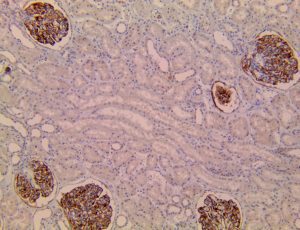

This activation induces inflammatory monocytes to highly express IL-6, starting a localized and then systemic cascade effect that results in hyperproduction of IL-6, which accelerates the inflammatory process. Because IL-6 also increases vascular permeability, excessive levels cause blood vessels to become very leaky. This, along with clotting factors released from vascular endothelial cells, stimulates the coagulation cascade, resulting in microthrombosis (tiny clots), which leads to ischemia and tissue death of the kidney, intestines, heart, liver, brain and extremities.